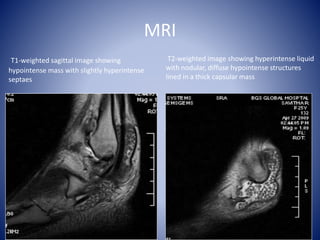

T1-weighted sagittal image showing

hypointense mass with slightly hyperintense

septaes

T2-weighted image showing hyperintense liquid

with nodular, diffuse hypointense structures

lined in a thick capsular mass